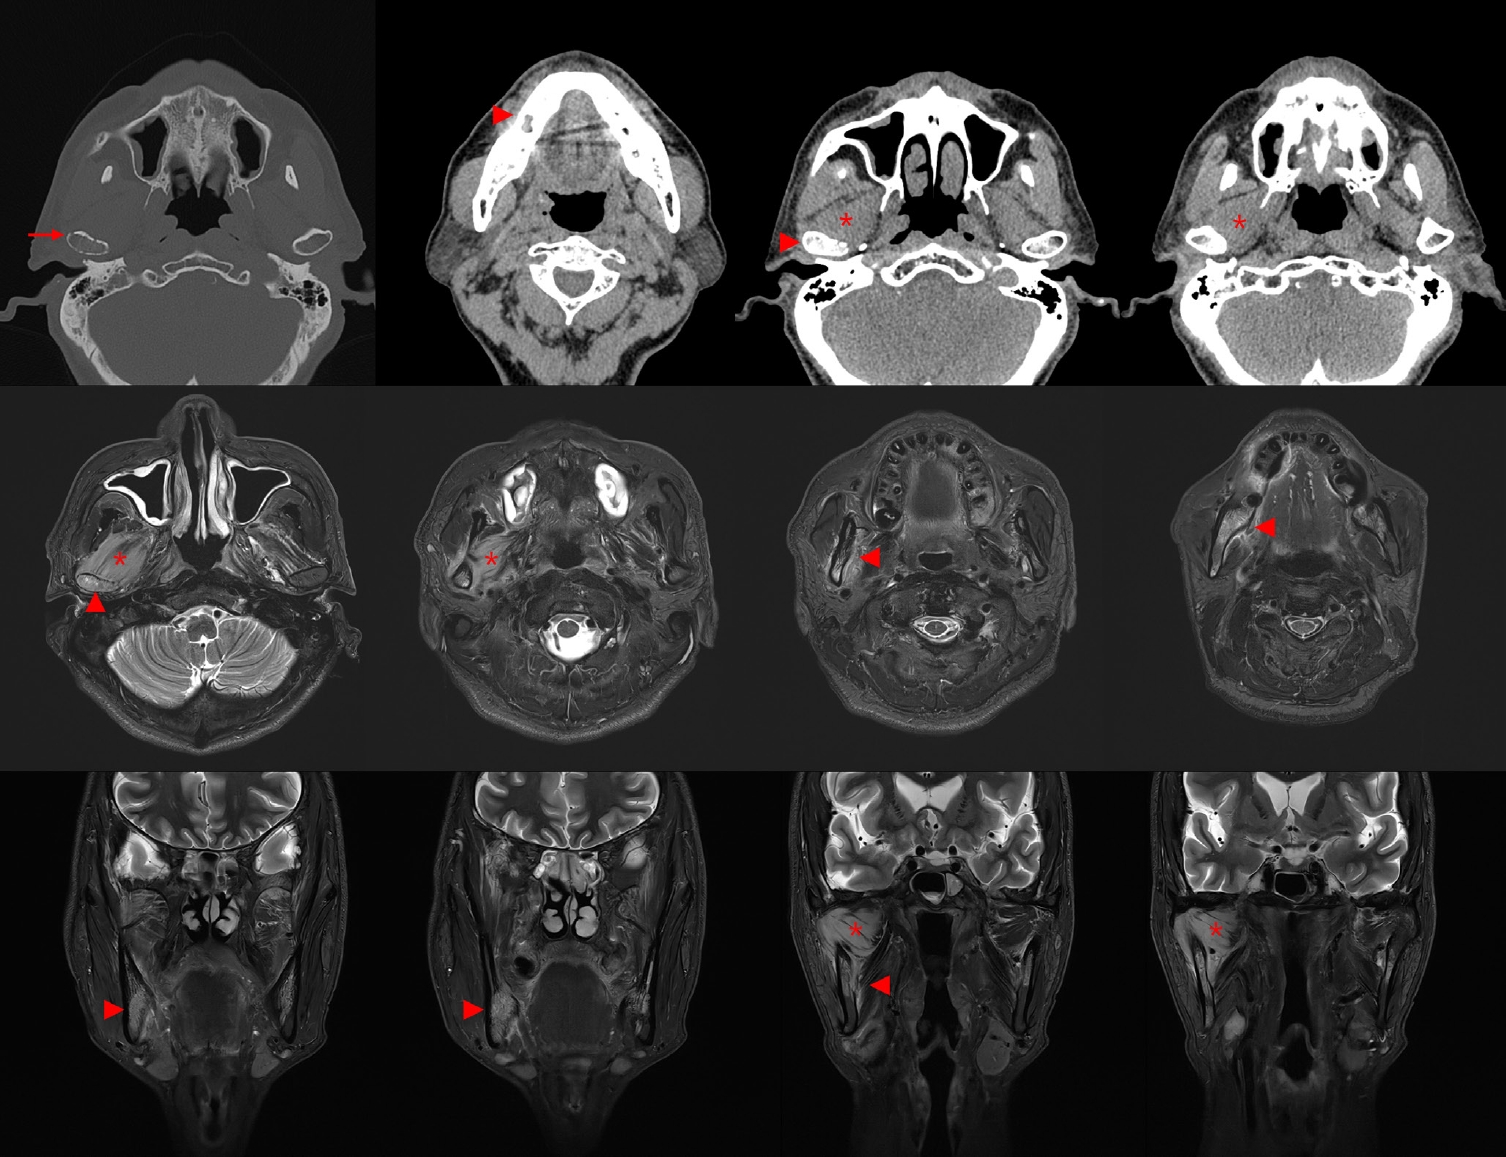

Diagnostic challenge in Burkitt lymphoma of the mandible initially misdiagnosed as osteomyelitis: a case report

Jiwon Do, Jin-Young Choi

J Pathol Transl Med. 2025;59(6):460-466.   Published online November 14, 2025

DOI: https://doi.org/10.4132/jptm.2025.09.18

• 3,429 View

• 112 Download

AbstractAbstract PDF

Burkitt lymphoma (BL) is a highly aggressive B-cell neoplasm that rarely involves the mandible in elderly without apparent immunodeficiency. We report a case of a 72-year-old male who presented with persistent mandibular pain following extraction of tooth #46. Initial imaging findings were consistent with incipient osteomyelitis, and the patient was treated with antibiotics. Despite treatment, pain persisted, and follow-up imaging revealed swelling and diffusion restriction in the lateral pterygoid muscle without evidence of a distinct mass. Biopsy revealed BL confirmed by immunohistochemistry: CD10+, BCL6+, c-MYC+, Ki-67 >95%, and negative for BCL2, MUM-1, and Epstein-Barr virus. Although c-MYC immunopositivity was demonstrated, fluorescence in situ hybridization for MYC rearrangement could not be performed due to limited tissue, representing a diagnostic limitation. Notably, the patient had no trismus despite deep muscle involvement, but complained of facial paresthesia and showed remote swelling in the scapular area during hospitalization. Systemic staging with imaging, cerebrospinal fluid cytology, and imaging revealed disseminated nodal and extranodal involvement including the central nervous system, corresponding to stage IV disease by Lugano classification. This case highlights the diagnostic challenge of distinguishing lymphoma from osteomyelitis and underscores the importance of considering malignancy in cases of refractory mandibular inflammation with atypical features.